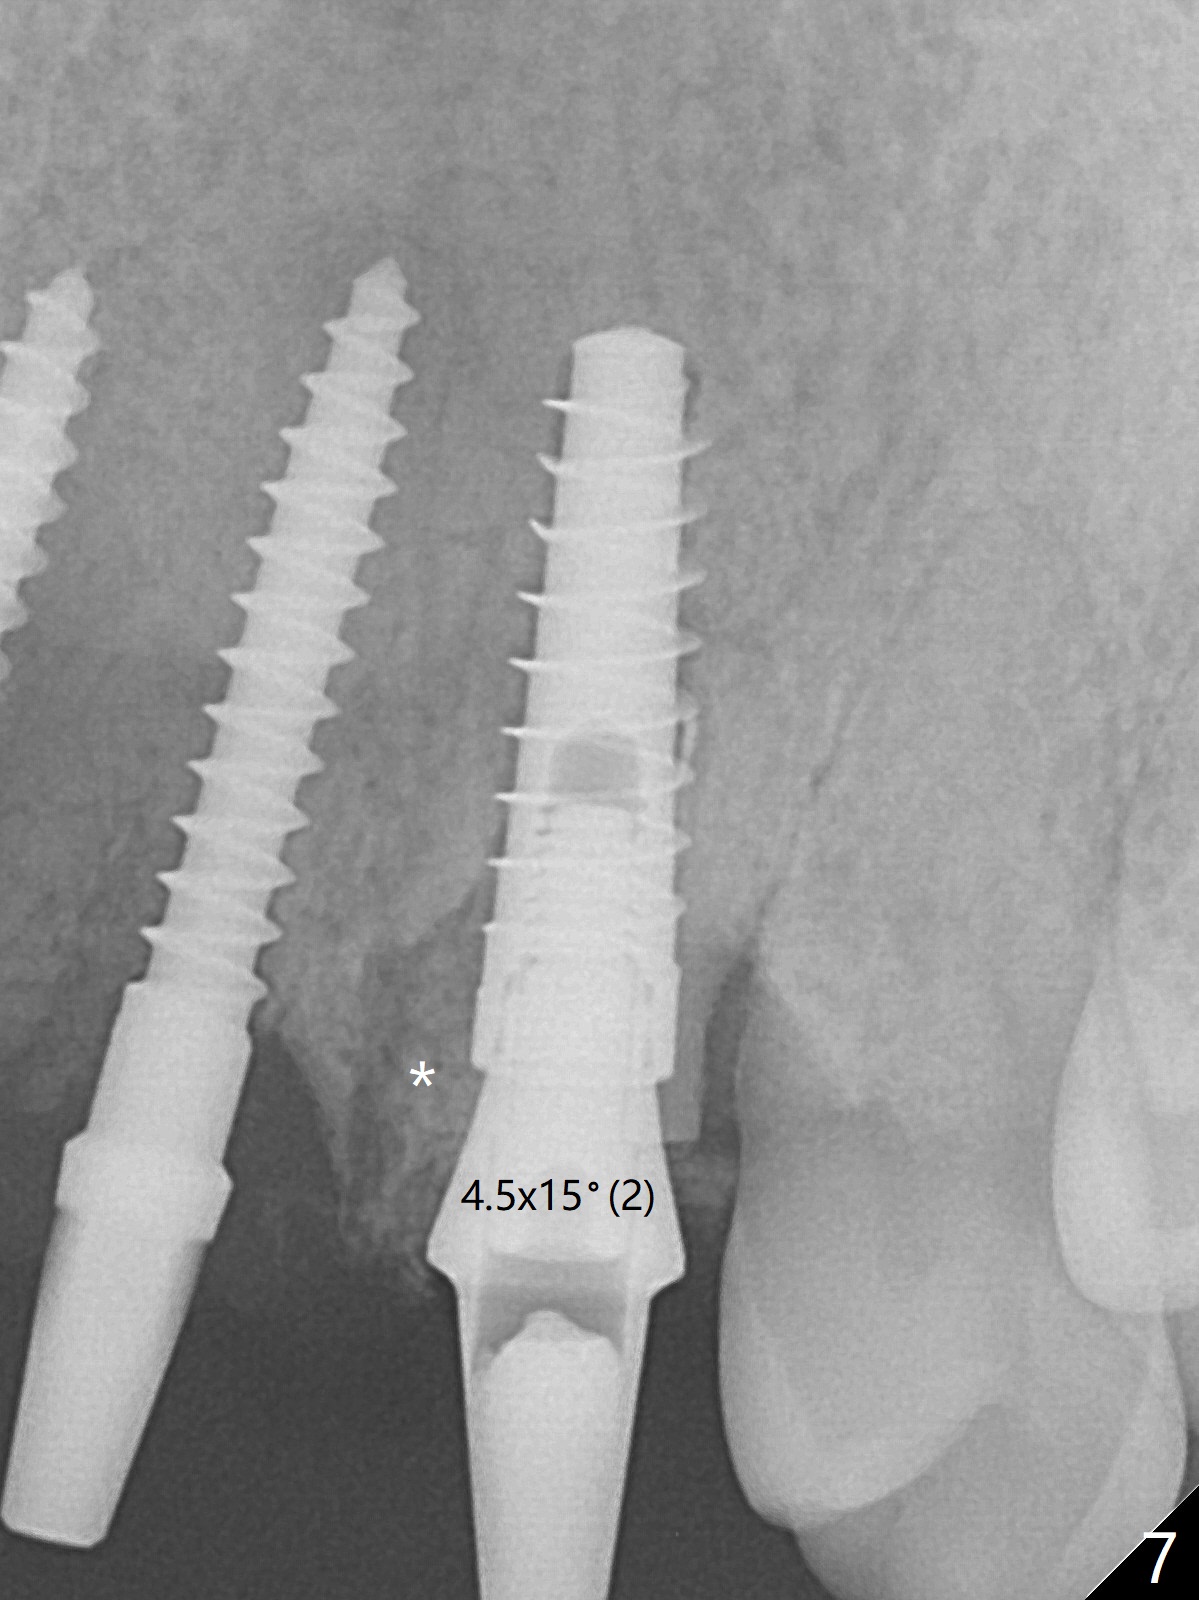

The buccal plate at #10 undergoes atrophy 9 months post immediate implant (Fig.1 *). To prevent the same post-extraction complication at #11, a technique called socket shield is going to be adopted. The buccal portion of the root (Fig.2-6 R, half-moon shaped) remains in place while a 3.5x13 mm implant is placed in the palatal portion of the socket (>50 Ncm). In fact the root is trimmed slightly subcrestal (Fig.6 C). It is assumed that there will be no or minimal bone resorption as long as the periosteum between the buccal plate and the remaining buccal root is not disturbed after tooth removal. After placement of a 4.5x15 degrees A (2mm) angled abutment and Vanilla graft (Fig.7 *), an immediate provisional is fabricated (using a central incisor crown form for #10 because of extra wide space of #11, Fig.8). There is no buccal plate atrophy at the canine 11 days postop (Fig.9). There is smooth transition from the grafted bone to the native bone 4.5 months postop (Fig.10). The buccal plate remains non-atrophic at the canine 4.5 months postop (Fig.11,12). CT taken 1 month post cementation shows that the implants at #10 and 11 are placed somewhat lingually (Fig.13,14 L (*: socket shield)). Gingival swelling is noted (Fig.15 *) with +Bleeding On Probing (^) 8 months post cementation (at the time of #21/24 impression). It appears that the socket shield (Fig.16 S) causes infection and loss of bone graft (*). The shield will be removed with an oblique accessory incision to save the papilla between #10 and 11 (Fig.17 black line). Prepare PRF for sticky bone (x1).